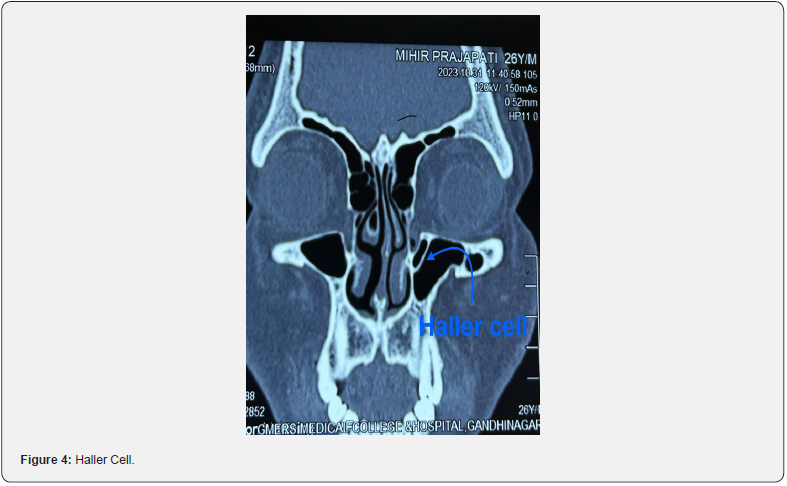

A retrospective study was conducted amongst 200 patients over a period of one year (2022-2023) at Sharda hospital Greater Noida . Patients with various symptoms of chronic rhinosinusitis were subjected to non-contrast enhanced Computed Tomography of nose and paranasal sinuses. Anatomic variations of the sinonasal cavities were assessed in the CT images, and prevalence of each was noted. The study included patients with age ≥ 18 having chronic rhinosinusitis and patient having chronic rhinosinusitis with or without polyposis who were advised NCCT nose and PNS after thorough examination. Patients having any previous nasal surgery or trauma, who did not consent for the study and patients less than 18 years were excluded from the study (Figure 2-4).

Albert von Haller first characterised Haller cells in 1765. They are ethmoid cells above and beside the maxillary sinus ostium growing into the floor of orbit [15]. Their frequency varies astonishingly, from 8% to 57%. The detrimental effect on maxillary sinus airflow is caused by limitation of infundibulum and maxillary ostium. Thus, establishing a link to recurrent maxillary sinusitis, making this variation clinically noteworthy [3].

Furthermore, orbital injuries after ethmoidectomy can be more likely when Haller cells are present [16]. Badia et al. [15] reported the presence of Haller cells in 10-15% Caucasian and 1-9% Chinese group respectively [15]. The Onodi cell (sphenoethmoid air cell), is a posterior ethmoid cell that is closely linked to the optic nerve. It pneumatises far laterally and somewhat superiorly to the sphenoid sinus.

The internal carotid artery and optic nerve are more vulnerable to injury when Onodi cells are present. Thus, identification before surgery is of utmost importance [3,13]. Its frequency is reported to fluctuate widely, from 2% to 50%. [16]. In Chinese population, presence of Onodi cells has been reported as 20-30 [15]. In the adult group, 48% of Onodi cells were found, according to Bansberg et al. [17]. In the current study, incidence of Haller cells was found in 5.0% and Onodi cells were found in 4.5% of subjects which comparable to previous studies.